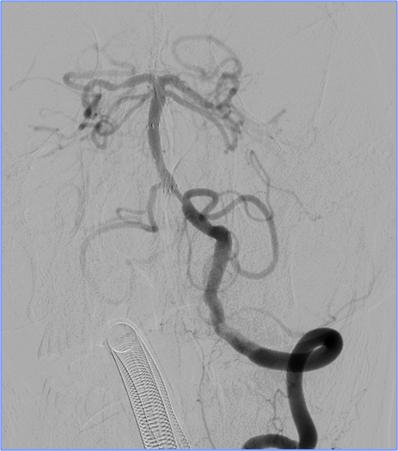

▼左椎动脉颅内段闭塞,脊髓前动脉代偿

▼右椎动脉颅外段闭塞

▼取栓后左椎动脉V4段残留狭窄

▼球囊成形,狭窄改善,不能维持

▼Wingspan支架置入